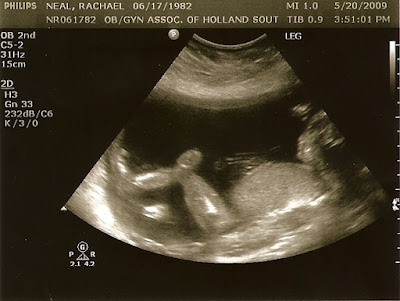

In baby news, it looks like everything is normal, except for the length of my baby's legs. Her femur registers in the 90th percentile. Hm...tall? I've also only gained 4 pounds this pregnancy. How that's possible with the amount of mint chocolate chip ice cream I've consumed, I don't know. But, I'll take it.